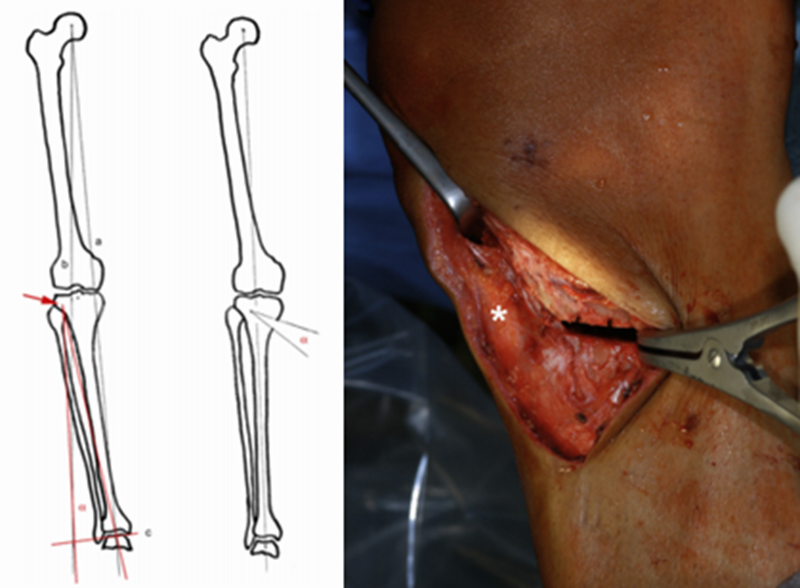

CWHTO术前计划

北京积水潭医院黄野教授等采用改良外侧闭合楔形胫骨高位截骨术治疗24例共35膝年龄均在45岁以下的膝内翻伴膝关节内侧间室轻度骨关节炎患者,术后平均胫股角(FTA)173.6°±2.4°,平均矫正11.0°±4.3°,截骨端均愈合,有1例延迟愈合。术后半年完全负重,无一例发生感染。2例出现腓总神经并发症(5.7%)。

采用改良外侧闭合楔形截骨,可以安全有效纠正内翻畸形,缓解骨关节炎疼痛,适用于年轻活跃的单侧或双侧膝内翻患者。但腓骨截骨的并发症仍然是需要考虑的因素之一。

如何确定矫正度数

Coventry建议内翻畸形至少矫正至股骨胫骨解剖外翻角8°;Hernigou等发现患者术后机械外翻角在3°-6°时临床效果较好;Fujisawa等发现如果HTO术后力线通过胫骨外侧平台的30%-40%,软骨破坏则不再进展,若通过胫骨平台外侧的62%,则为最佳点,此点被定义为Fujisawa点。

A.双平面截骨,第一刀沿水平面在胫骨后2/3进行截骨,保留外侧合页约10mm,第二刀沿冠状面在胫骨前1/3进行截骨,两刀截骨角度呈110°。B.撑开器逐渐缓慢加大骨缝,注意保留外侧合页。C.力线杆定位,撑开至力线杆经过Fujisawa点。D.进行内固定。